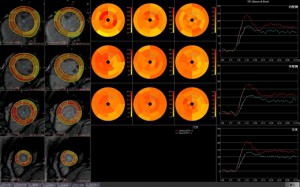

○MR心筋パフュージョン解析(図3)